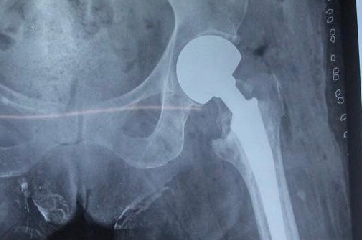

Todo tipo de cirugías traumatológicas y ortopédicas.